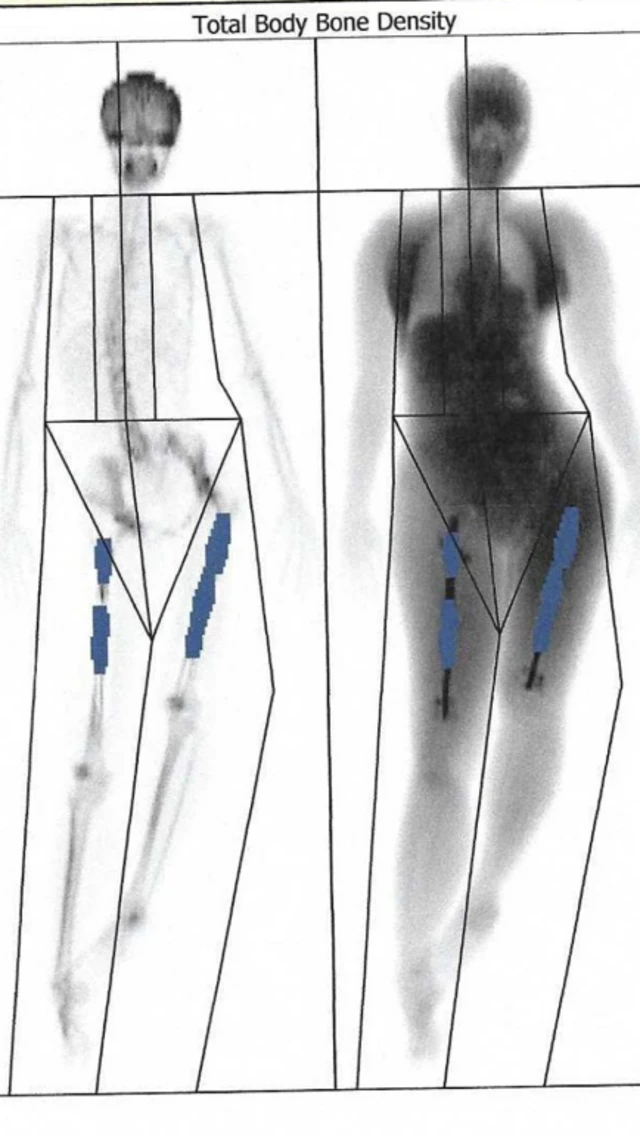

या थोडा त्रास होतो, कारण प्रक्रियेत पायाच्या हाडाचे दोन भाग करून मधे मेटल रॉड बसवला जातो.

हळूहळू त्या हाडांच्या मधे बसवलेल्या मेटल रॉडची लांबी वाढवली जाते, जेणेकरून रुग्णाची लांबी वाढेल.

नंतर हाडाचे हे दोन्ही भाग पुन्हा जुळतात आणि त्यांच्यामधील खाली भाग भरला जातो. पण ऑपरेशनची ही प्रक्रिया खूप किचकट असते.

इलेनची भीती खरी ठरली, दुसऱ्या दिवशी स्कॅन केलं असता त्यांच्या डाव्या पायात लागलेला एक नेल हाडाला छेदून आरपार गेला होता. फेमर (पायाच्या वरच्या भागाचे हाड) तोडून बाहेर आले होते. फेमर शरीरातील सर्वात मजबूत हाड असतं.

सहा आठवड्यांनंतर त्यांचे पाय स्कॅन केले गेले आणि त्यामध्ये उजव्या पायाच्या हाडांची वाढ थांबल्याचं दिसून आलं. या पायात, फेमरचे दोन तुकडे रॉडच्या मदतीने जोडले होते.